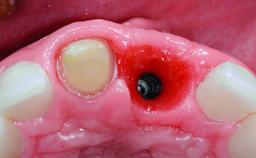

Replacement of a Compromised Upper Right Central Incisor: Hard- and Soft-tissue Augmentation, Late Placement of an RC Bone Level Implant

A 36-year-old male patient with a compromised maxillary central incisor was referred by his general dentist for consultation. The patient’s chief complaints were the gradual debonding of a temporary crown on the right central incisor and unsatisfactory esthetics due to an increasing diastema between the right central and lateral incisors. The patient reported a traumatic event some years previously, when a crown had been placed after root-canal treatment. The referring dentist wanted to provide a new crown restoration, but was concerned about the condition of the residual root. Anamnesis was negative for any other dental or periodontal pathology in the remaining dentition. The patient reported taking no medications: He was a smoker (10 to 15 cigs/day) and had realistic esthetic expectations.

Bone Augmentation Horizontal|Simultaneous|Staged

Augmentation Materials Xenogenous|Membrane

Bone Volume Deficient horizontally, requiring prior grafting